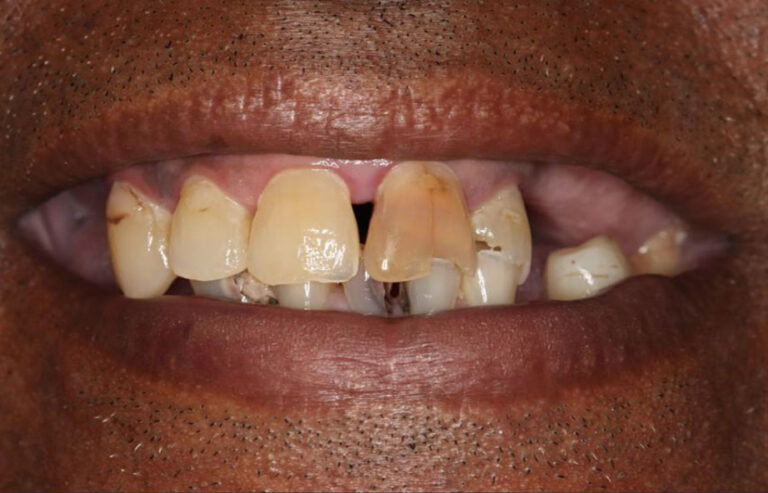

Consultation & 3D Scan

We begin with a comprehensive clinical evaluation and advanced 3D imaging to assess bone quality, anatomy, and functional needs. This allows us to design a fully customized treatment plan from day one.